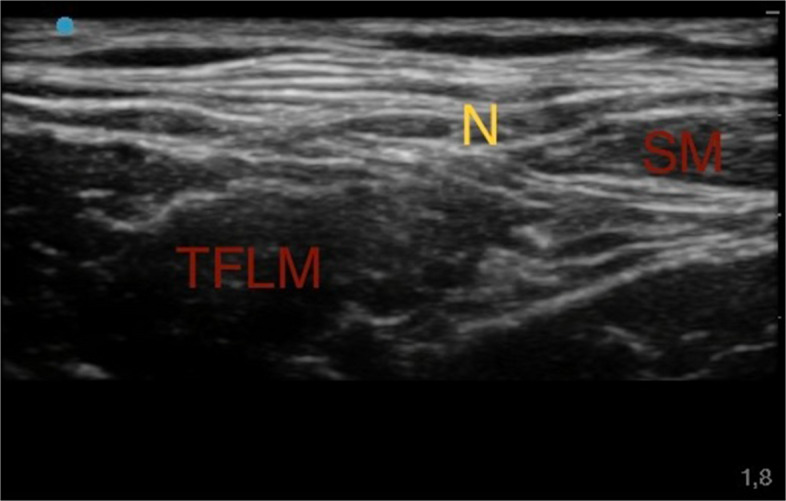

Ultrasound Lateral Femoral-Cutaneous Nerve Block

As second step, after identification of the femoral artery and vein, a lateral probe slide helped visualize the space between the Fascia Lata, Fascia Lata Tensor Muscle and Sartorius Muscle. At this level the lateral femoral-cutaneous nerve with its distinctive "eye" appearance was identified. From the lateral side of the transducer, an 80-mm-long 21-gauge 30° tip (Pajunk) to ensure optimal visualization of the needle tip. An anesthetic solution of Ropivacaine 0.375% (dose 1.875 mg) plus Mepivacaine 1% (dose 5 mg) (total volume 1 ml) was subsequently injected (Fig. 2) [42].

Fig. 2.

Ultrasound lateral femoral-cutaneous nerve block. Sartorius muscle (SM); Tensor fasciae latae muscle (TFLM); Lateral Femoral-Cutaneous nerve (N)